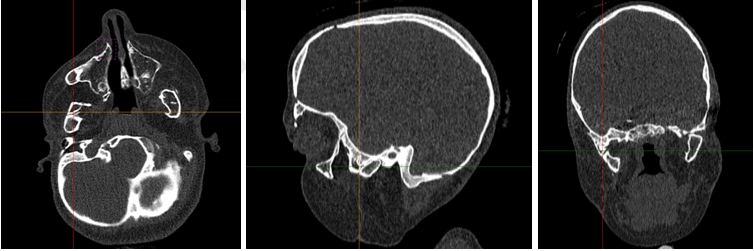

Prior to her last surgery, the patient had reankylosis of her bilateral TMJ resulting in severe limited jaw opening that required repeat mandibular osteotomies (Figure 1). For the previous mandibular osteotomy, Brainlab intraoperative CT-guided navigation system was used to aid in the preoperative planning of localizing and assessing the extent of the TMJ fusion. The surgery was completed in nine hours with no complications. For most recent mandibular osteotomy, SuRgical PlannerTM was used in conjunction with Brainlab intraoperative CT-guided navigation system (Figure 2). This additional surgical guidance tool allowed us to rehearse the operation for TMJ resection and also assess the extent of our dissection, thereby accelerating operative efficiency (Figure 3). Additionally, based on principle of CT scanning Hounsfield unit, the SRP simulator can display or hide slices of tissue in real time, thereby allowing us to visualize surrounding skull base, vessel, and soft tissue anatomy as well as the location of our surgical probe to minimize skull base complications [12]. Overall, the operative time was four hours, a notable decrease from nine hours previously. There were similar scars noted from prior surgeries and no complications. The exact same sequence of surgery and placement of Matthews device was performed for these two operations to justify the comparison.

Figure 1: Preoperative axial, sagittal and coronal computed tomography images demonstrating bilateral temporamandibular joint ankylosis, right more prominent than left.